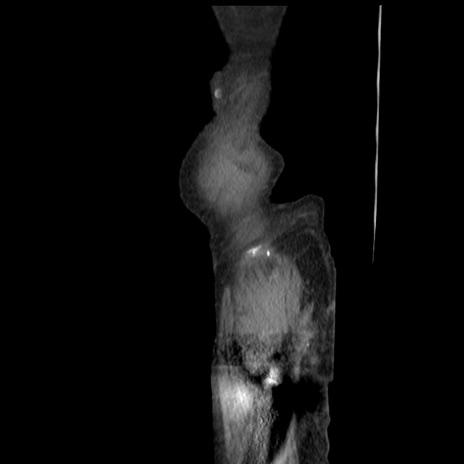

横断像